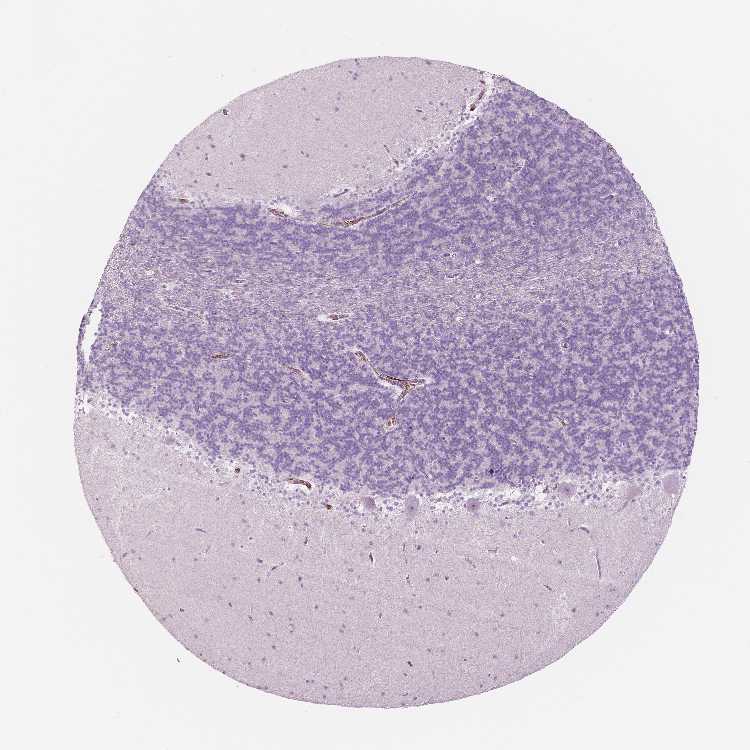

BRAIN CEREBELLUM Show tissue menu

CEREBELLUM - Expression summary

CEREBELLUM - Antibody stainingi

Antibody staining in the annotated cell types in the current human tissue is reported as not detected, low, medium, or high, based on conventional immunohistochemistry profiling in selected tissues. This score is based on the combination of the staining intensity and fraction of stained cells.

Each image is clickable and will lead to virtual microscopy that enables deeper exploration of all samples and also displays staining intensity scores, fraction scores and subcellular localization as well as patient and tissue information for each sample.

Antibody HPA012023Antibody HPA046717

Purkinje cells Not detectedNot detected

Cells in granular layer Not detectedNot detected

Cells in molecular layer Not detectedNot detected